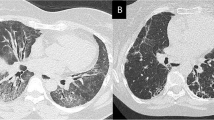

We selected 98 samples from patients with SSc initially recruited for a previous study (2010 to 2018) focusing on biomarkers in SSc from our ambulatory care policlinic at CHU Liege. The patients were divided into 2 groups: SSc patients without any lung involvement (SSc, n = 67) and patients suffering from SSc associated with interstitial lung disease (SSc-ILD, n = 31). The diagnosis of SSc was made according to the international recommendations of ACR/Eular [20, 21]. Patients were divided in two groups according to their HRCT scan to determine the presence of ILD. Lung involvement was evaluated using the respiratory function test, HRCT scan, bronchoalveolar lavage (when available), and the clinical history of the patient. We excluded all other causes of interstitial lung disease (such as asbestosis, idiopathic pulmonary fibrosis, hypersensitivity pneumonitis, or toxic pneumonitis). Then, we compared the baseline level of biomarkers (T1) with the time 2 (T2) level of biomarkers collected between 6 and 18 months after T1 (median: 11 months and 22 days).